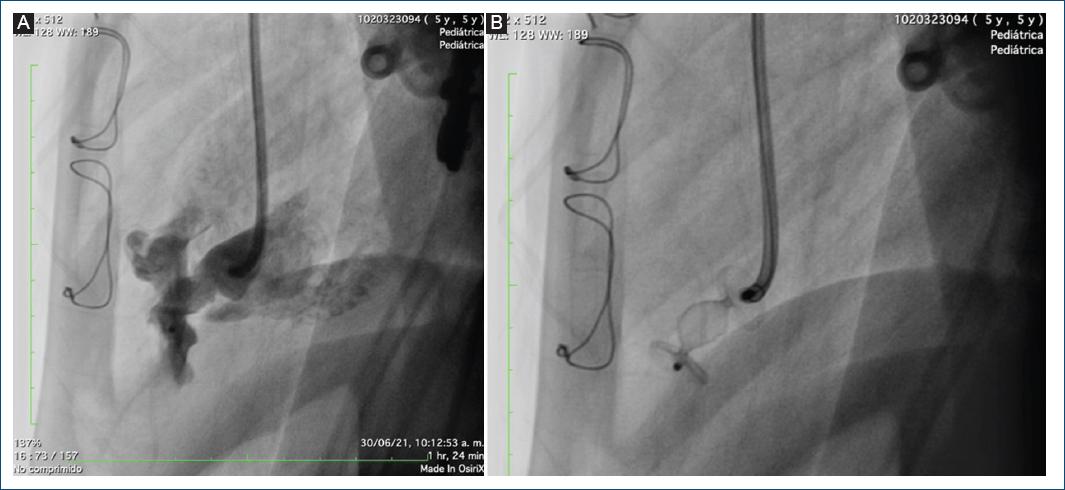

Se llevó de nuevo el caso a junta médico-quirúrgica, donde se consideró el cierre del defecto por vía endovascular (Fig. 5). Para ello, se avanzó una guía hidrófila dentro del divertículo y sobre esta se pasó un catéter non taper hasta el cuerpo del divertículo. Se realizó angiografía en proyecciones oblicua derecha y lateral, observando el gran divertículo con un boca proximal tipo túnel.

Figura 5 Ventriculografía izquierda con ventrículo de morfología izquierda, posterior, con segmento apical con divertículo gigante, con trabéculas en su interior, con fuga residual del parche de pericardio, visualizada previamente en la ecocardiografía.

Para aclarar la anatomía, se pasó una guía Whisper 0.014 y sobre esta se llevó un balón Tyshak de 10 × 20 mm, el cual se infla en forma manual, observando que la boca del divertículo medía 4 mm.

Se decidió ocluir con un Amplatzer Vascular Plug II (AVP II) de 10 mm, un dispositivo oclusor cilíndrico autoexpandible que se ajusta a la forma del vaso con una malla flexible de alambres de nitinol con marcas de platino en ambos extremos, sin material trombogénico en su interior (Fig. 6).

Figura 6 Medidas del balón y decisión de implantación de un dispositivo Amplatzer Vascular Plug, teniendo en cuenta la necesidad de un dispositivo con cintura por la configuración de la lesión en túnel.